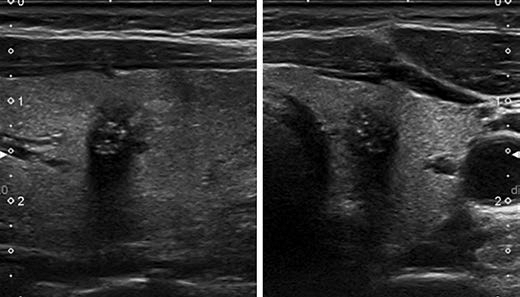

KTIRADS